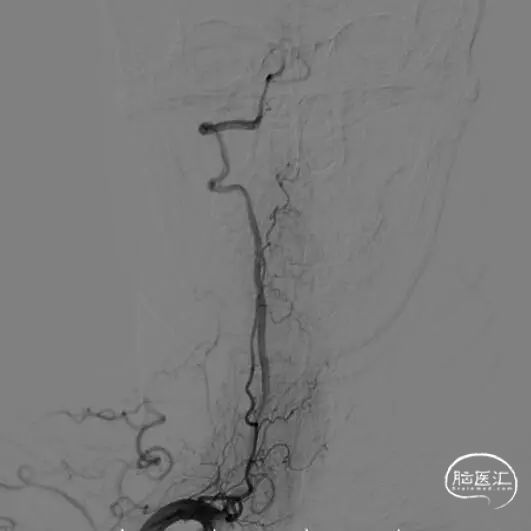

右侧椎动脉正位和侧位。

左侧椎动脉正位和侧位。

左侧颈总动脉正位和侧位。